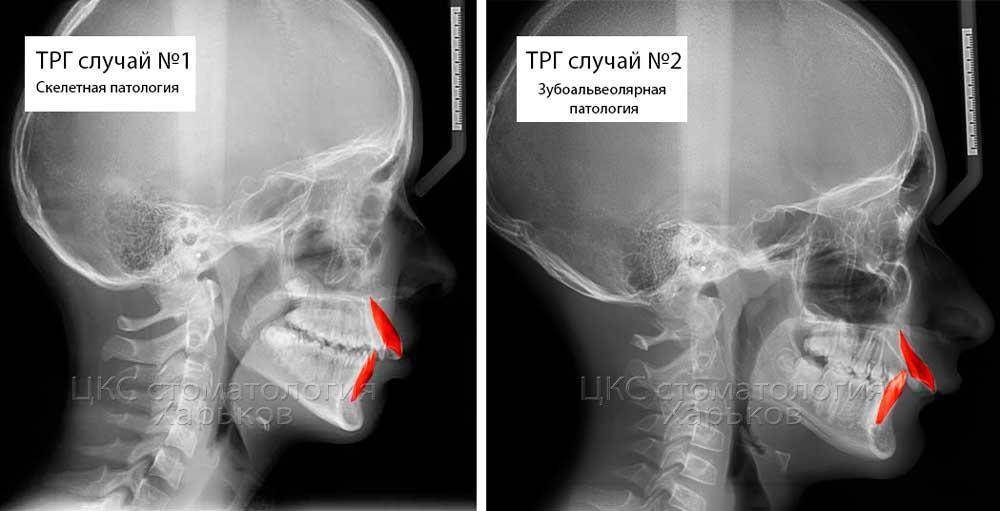

Dmitry002442 Опубликовано 22 июля, 2023 Автор Поделиться Опубликовано 22 июля, 2023 7 часов назад, АнтонТЛТ сказал: Ортодонтической миниимплантов помогают в перемещении зубов еще вопрос такой. У меня скелетная или зубоальвеолярная патология? просто нашел вот такое изображение и по нему не понимаю как определить патологию. Ссылка на комментарий

АнтонТЛТ Опубликовано 22 июля, 2023 Поделиться Опубликовано 22 июля, 2023 Нужно сходить на консультацию к ортодонту и полноценную диагностику. Выложенные Вами данные это малая часть диагностики. Ссылка на комментарий